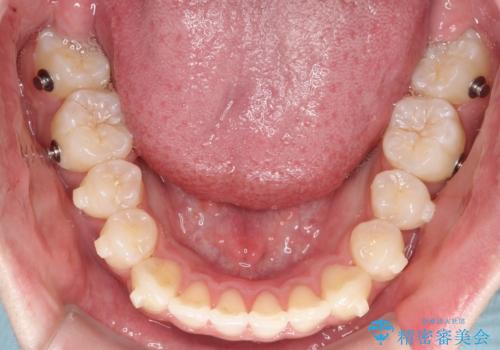

- 前歯が出ていることを主訴に来院されました。

臼歯関係が上顎前突傾向のため、上顎小臼歯を抜歯してインビザラインにて治療を行いました。

臼歯の咬合を作るために治療終盤ではゴムかけを行なっています。